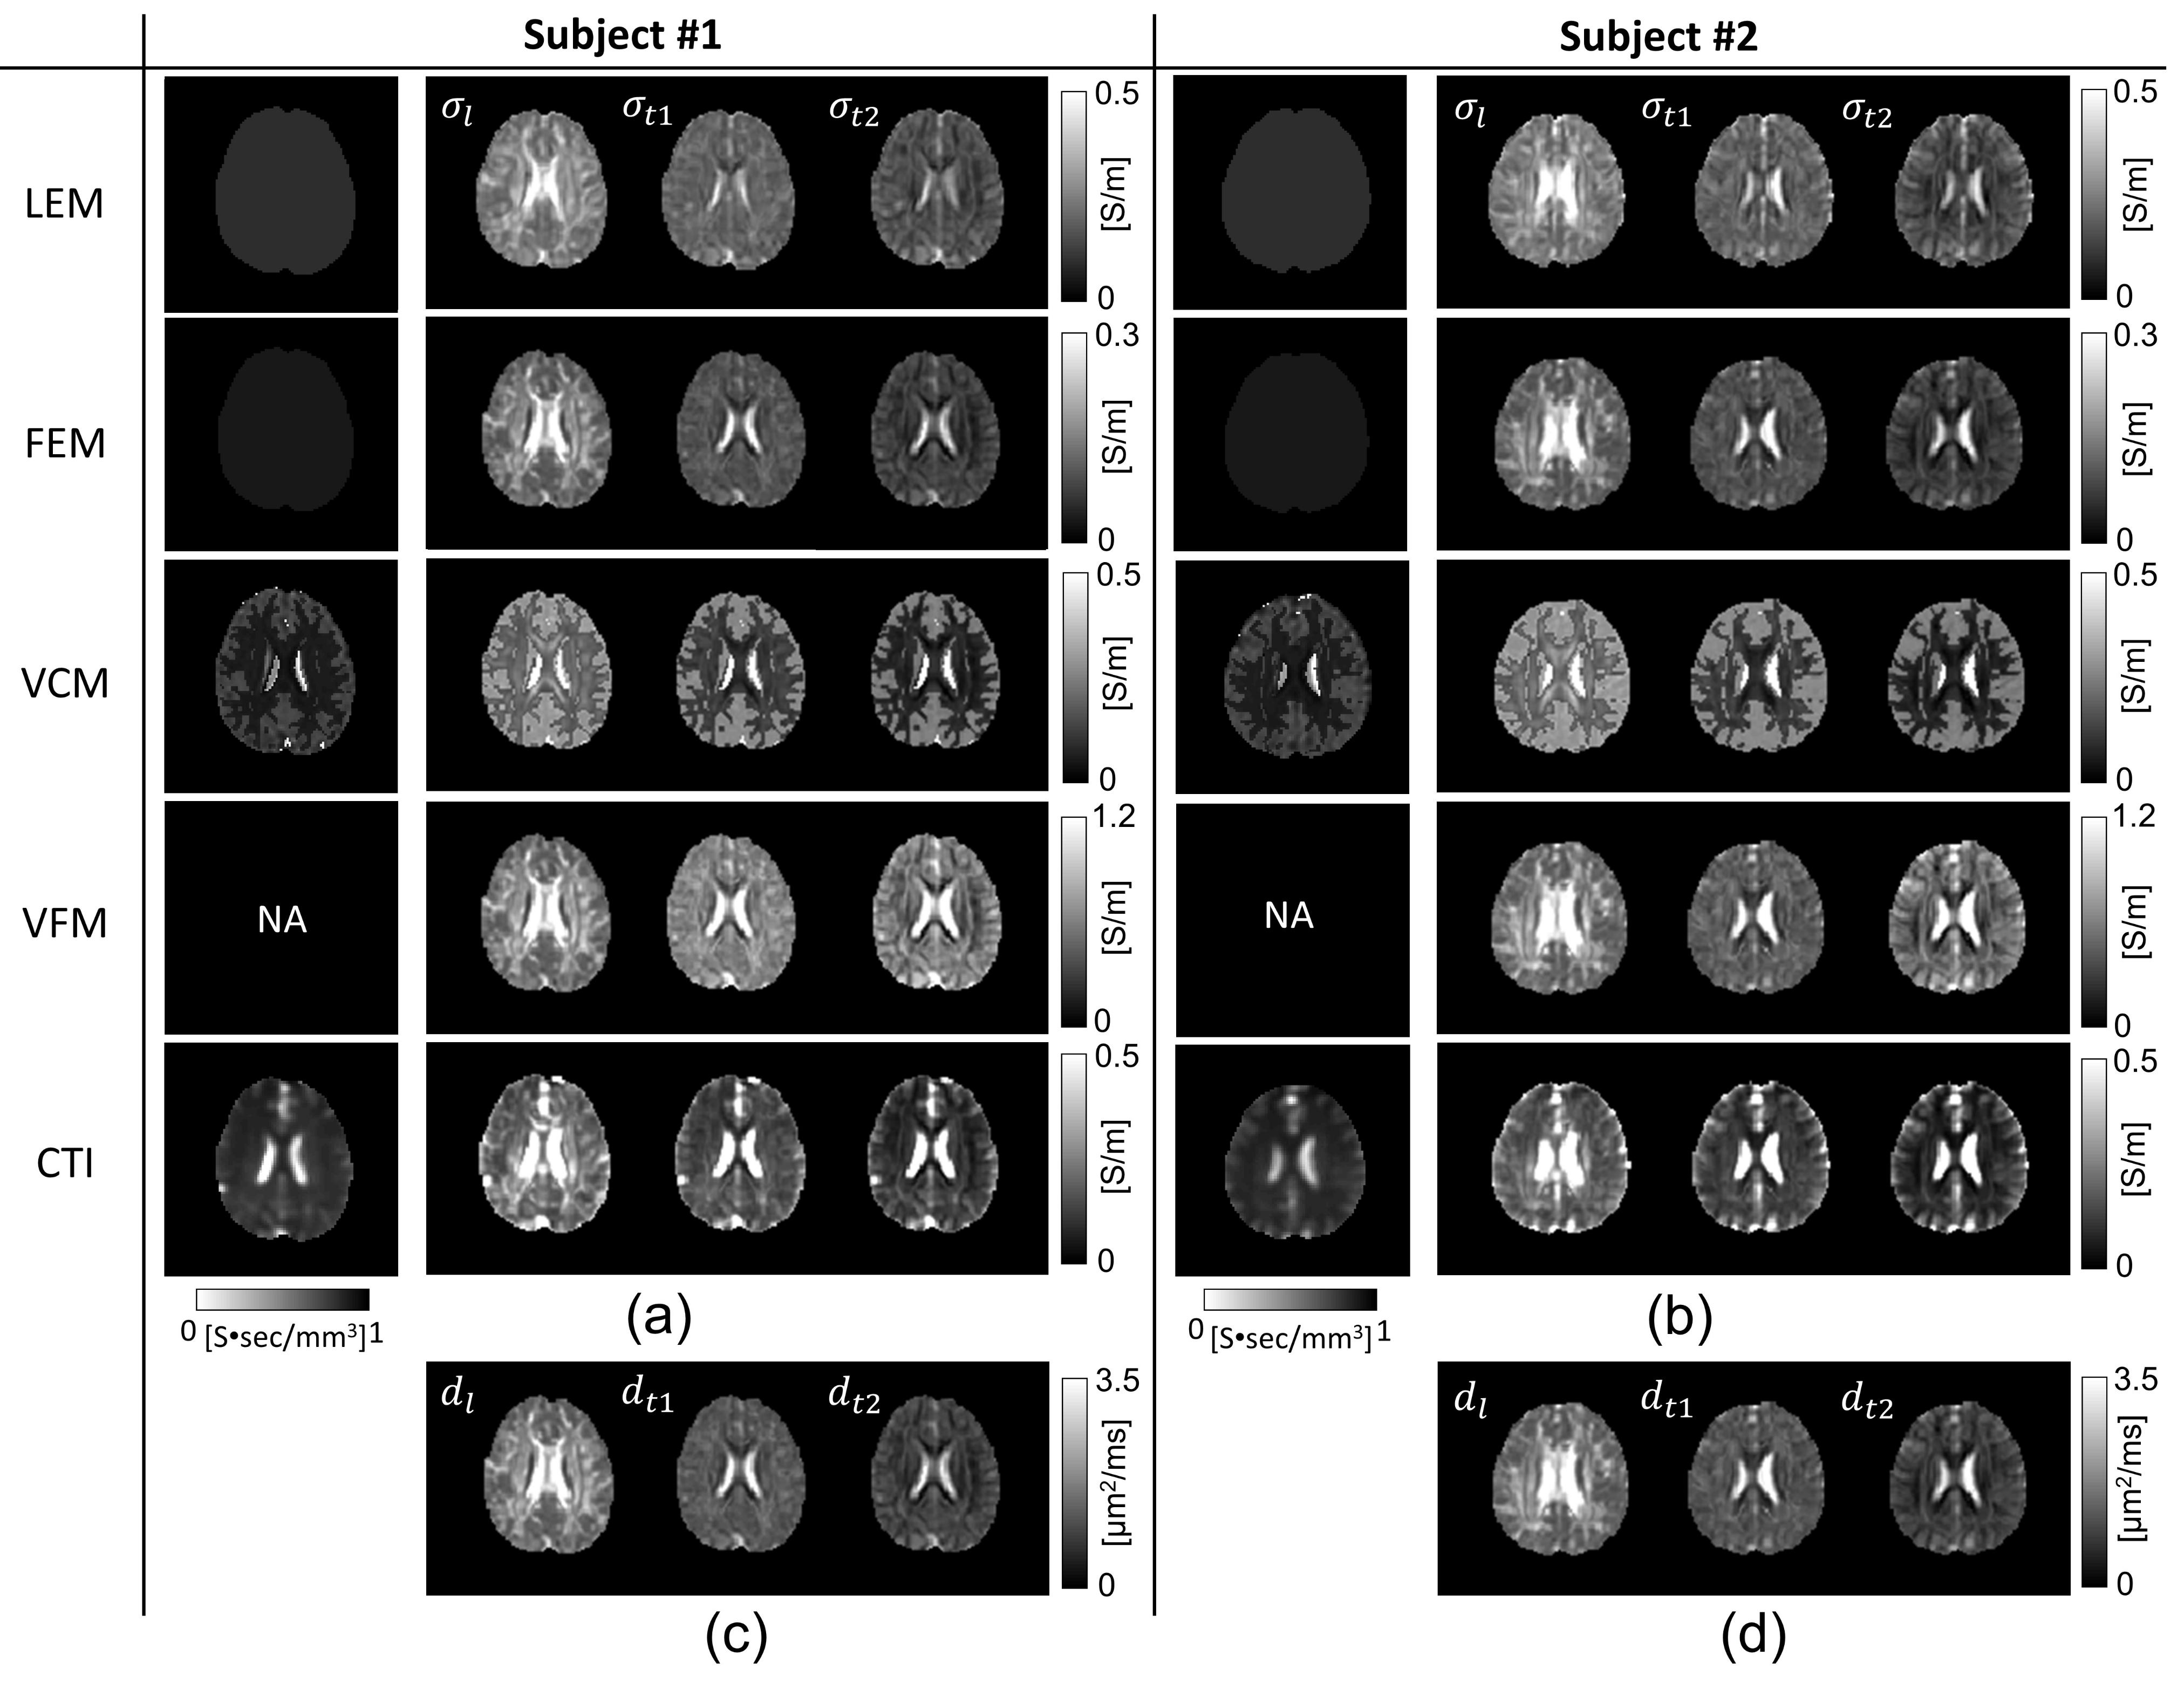

4.2. Five Human Brains